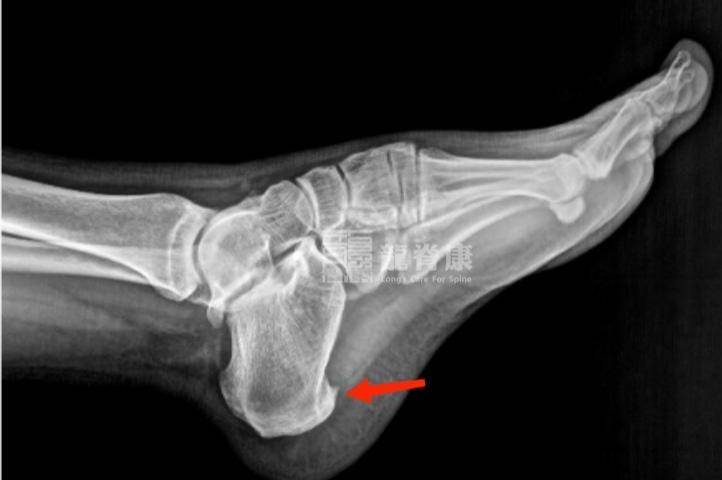

2、足跟骨刺

骨刺常被认为是尖锐的东西扎在肉里,其实它本身不直接引起疼痛。骨刺是身体的一种代偿反应,当足底筋膜在跟骨附着点被过度牵拉时,身体会自我修复,时间长了可能钙化形成骨刺。通常是在足底筋膜炎的基础上出现的。

症状和足底筋膜炎非常相似,也是脚跟底部痛。但骨刺患者的疼痛点可能更固定,按压时有明显的尖锐感。通过X光片可以明确看到跟骨前方有骨性突起。

很多人看到X光片上的骨刺就认为是它导致疼痛,其实疼痛主要还是来自筋膜的炎症。治疗的重点也是消除炎症和改善力学环境,而不是切除骨刺,除非骨刺非常大或保守治疗无效。